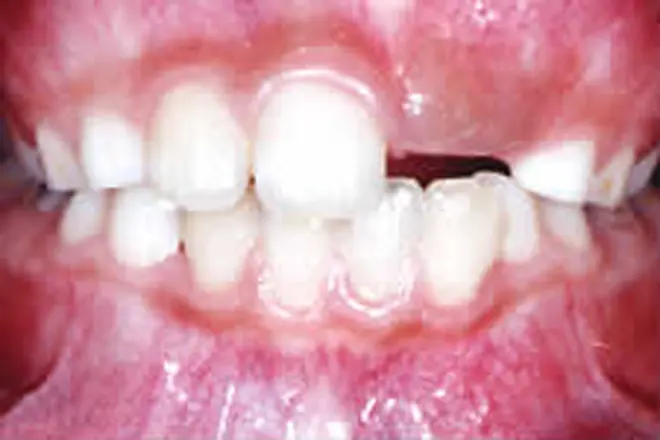

子どもの矯正 治療例4

奥歯が噛み合った状態でも、前歯に隙間ができています。

乳歯が多数あると全体矯正ができないので、歯の裏側に舌突出防止装置を付けました。これにより、舌が前に出る圧力を押さえました。

噛み合わせが整い、デコボコも解消されました。

| 患者さまの年齢・性別 | 13歳・女性 |

| 治療期間 | 2年 |

| 治療費(税込) | 946,000円 |

| 主訴 | 前歯が噛まない |

| 診断名・主な症状 | 開咬 |

| 治療に用いた主な装置 | 舌突出防止装置・表側矯正装置 |

| 治療内容 | 歯の裏側に舌突出防止装置を付け、治療と同時に舌癖を改善するトレーニングを実施しました。 |

| 抜歯部位 | 非抜歯 |